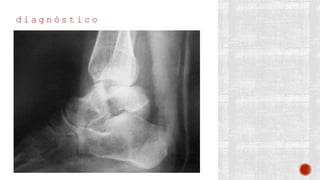

d i a g n ó s t i c o

¬ Clínico

¬ Radiológico

- AP de tobillo

- Lateral de tobillo

- De mortaja

- AP de pie

- Lateral de pie

- Oblicua de pie

- Proyección de Canale

- TAC

- Gammagrafía ósea con tecnecio 99

- RM